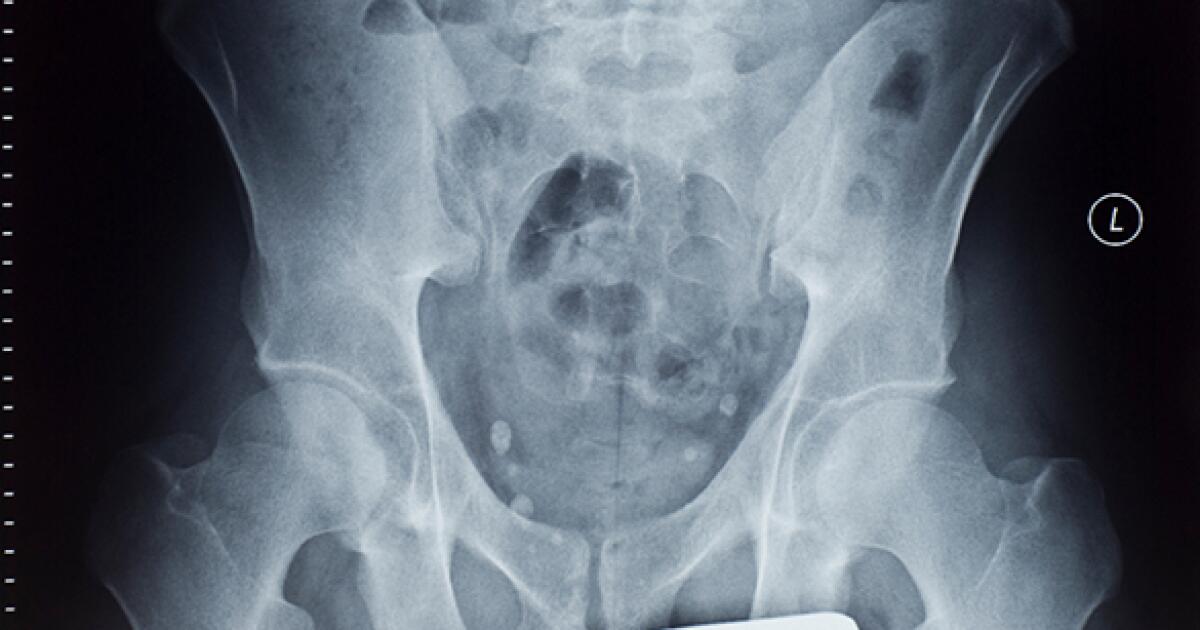

An X-Ray isnt sensitive enough.

CT is considered the best imaging modality for staging ovarian cancer. An x-ray uses small doses of radiation to make an image of parts of the body on film. They produce sex hormones regulate the menstrual cycle and produce eggs.

An x-ray is a way to create a picture of the structures inside the body using a small amount of radiation. Ovarian tumors may be primarily cystic solid or mixed. Computed tomography CT scan.

X Ray Of The Pelvis Purpose Procedure And Risks

Xray Pelvis Show Ovarian Cancer Stock Photo Edit Now 498028849

Ovarian Cyst Seen On Plain Abdominal Radiograph